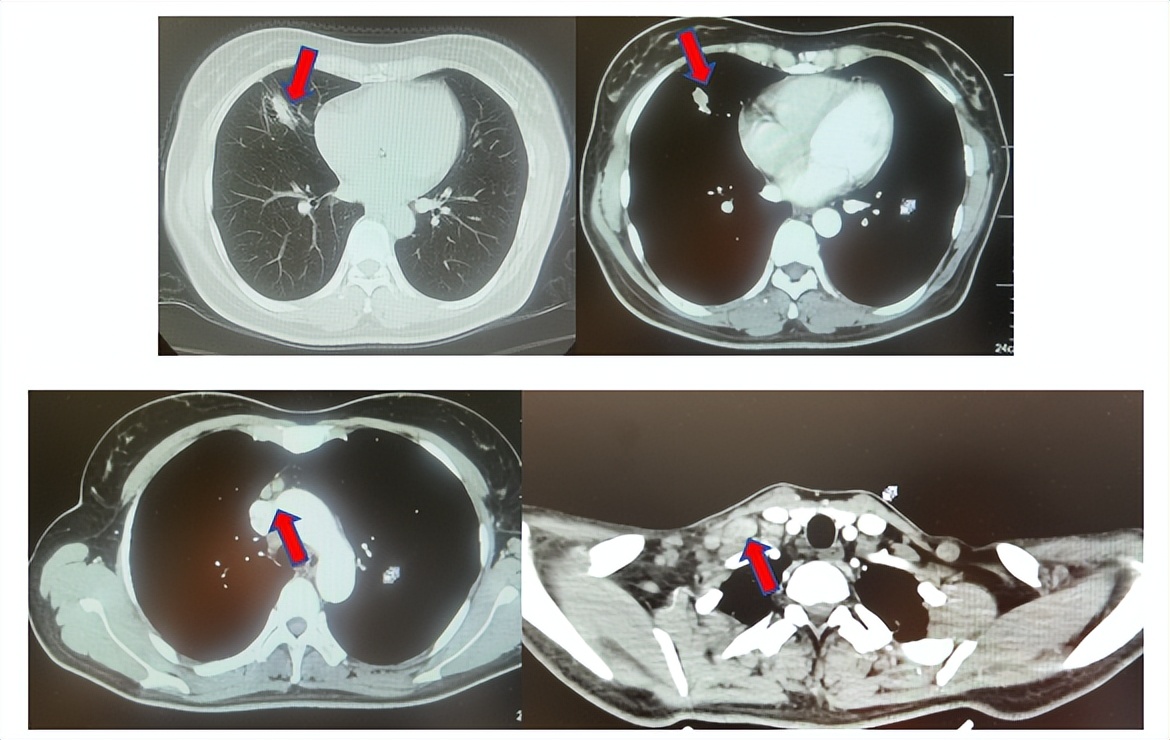

患者符合我科正在开展的“一项比较Durvalumab治疗与标准治疗(含铂化疗)用于PD-L1高表达晚期非小细胞肺癌患者一线治疗的III期随机、开放、多中心研究”的入组要求,经知情同意进入该试验,经随机进入化疗组,于2017年7月至2023年12月应用培美曲塞联合卡铂治疗6周期,后行培美曲塞单药维持治疗105周期,肺内CT现实右肺下叶病灶缩小90%,颅内病灶缩小100%,最佳疗效肺内病灶PR及颅内病灶达CR(图2),于2023年2月复查CT,肺内病灶逐渐增大,至2024年1月,疾病进展出组该临床试验,一线无进展生存为78个月。

图2:上两图分别展示2021年5月患者达到最佳疗效时肺CT肺窗及纵隔窗肺内病灶及肺门淋巴结影像,下三图表示最佳疗效时脑MRI影像

患者进入到二线治疗,该患者再次符合我科“优替德隆对照多西他赛治疗含铂化疗失败的局部晚期或转移性非小细胞肺癌的III期、开放、随机对照临床试验”经随机进入多西他赛组,截止至目前患者已行多西他赛治疗19周期,期间评效为SD(图3),二线无进展生存至今为14个月,患者总生存期截止目前超过92个月(整体治疗过程如图4所示)。

图3:上两图分别展示2024年1月患者一线进展时肺CT肺窗及纵隔窗肺内病灶影像,下两图表示2024年12月患者二线治疗间期评效时肺CT肺窗及纵隔窗肺内病灶影像